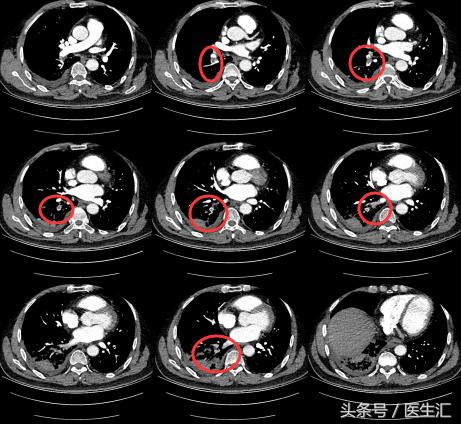

因为发现患者1 个月前有外伤手术史,那么是否可能有其他可能?所以我们给患者做了一个CTPA。

【注意】

每一个层面都有肺动脉的充盈缺损。